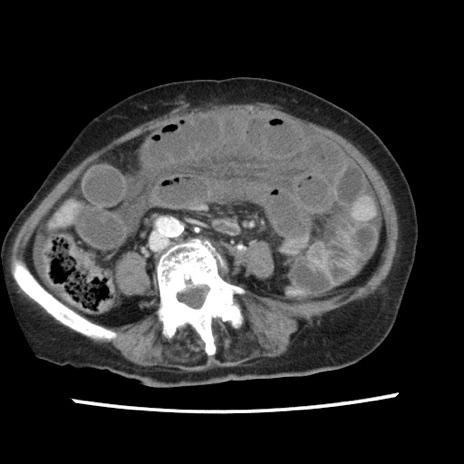

症例1(横断像)

【症例】80歳代女性

【主訴】腹痛

【現病歴】8時間前から腹痛あり来院。

【既往歴】糖尿病、脂質異常症、子宮体癌にて子宮全摘術

【身体所見】意識清明・会話良好だが腹痛で苦悶様、全腹部にわたって反跳痛と圧痛あり

【データ】WBC 13600、CRP 0.14、LDH 224、CK 90